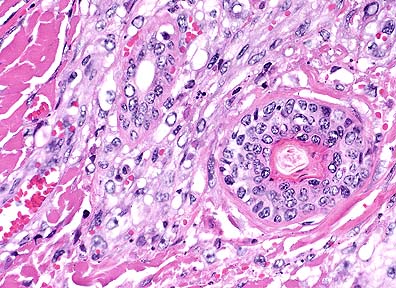

Multiple eosinophilic intracytoplasmic inclusion bodies (Negri bodies) in the cells of the Purkinje layer in the cerebellum of a 6-month old foal. (HE, 400X, 59K)

In the cerebrum, occasional vessels are surrounded by thin perivascular cuffs of lymphocytes. The cerebral cortex is mildly hypercellular (glial cells) and occasional neurons contain eosinophilic intracytoplasmic inclusion bodies that vary from 2-7 æm in diameter. In sections of cerebellum there is segmental loss of Purkinje cells; many remaining Purkinje cells contain single to multiple eosinophilic inclusions similar to those seen in cortical neurons.

Histologically, rabies infection is characterized by a nonsuppurative encephalomyelitis and ganglioneuritis with intraneuronal eosinophilic inclusion bodies (Negri bodies). The typical reaction is perivascular cuffing, gliosis and neuronal degeneration. The microscopic findings can vary greatly from case to case and from species to species with carnivores generally showing a more severe reaction than herbivores. In this case, inflammation is minimal. Negri bodies are generally 2-8 mm, discrete to amorphous inclusions with a clear, thin halo that range from none to several per cell. The location of neurons that contain Negri bodies is important and differs with the species of animal affected. Generally, the hippocampus is the most common site for finding Negri bodies in carnivores, whereas the Purkinje cells of the cerebellum are most often affected in herbivores and humans. Negri bodies have also been found in ganglion cells of the adrenal medulla, retina, and salivary gland. In some species, care must be taken to differentiate Negri bodies from nonspecific inclusions that have been found in the pyramidal cells of the hippocampus or the lateral geniculate nucleus neurons in cats, skunks, and dogs and in the larger neurons of the medulla and spinal cord of old sheep and cattle; these inclusions are often smaller than Negri bodies. Dogs also may have cytoplasmic lamellar bodies in neurons of the thalamus and cerebellar cortical Purkinje cells.